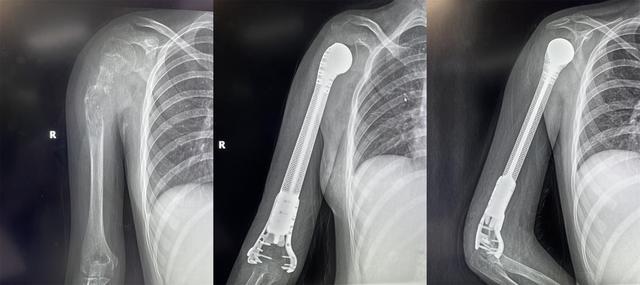

13歲少女患骨肉瘤面臨截肢,3D打印肱骨假體治療成功保肢

2022年4月19日,獲悉,西安市紅會(huì)醫(yī)院骨病腫瘤科為一名13歲小患者成功實(shí)施了肱骨惡性腫瘤切除3D打印假體重建術(shù)。165751qartxm1zze19w2ha.jpg

小欣(化名)因右肱骨中上段腫瘤,飽受疾病折磨,幾經(jīng)輾轉(zhuǎn)后來到西安市紅會(huì)醫(yī)院就醫(yī),活檢確診為 右肱骨中上段骨肉瘤 。

骨病腫瘤科楊團(tuán)民主任介紹,骨肉瘤是一種好發(fā)于兒童長骨的骨端高度惡性的原發(fā)性腫瘤,治療原則為手術(shù)結(jié)合化療、放療綜合治療。 由于腫瘤范圍較大沒有生物重建可能,也沒有相關(guān)腫瘤假體,保肢難度很大,一直是業(yè)內(nèi)難題,所以普遍選擇截肢。 165751f8i13tpusqaqduut.jpg

對(duì)于一個(gè)13歲的女孩來說,截肢必然會(huì)對(duì)孩子的心靈帶來巨大陰影,同時(shí)小欣父母表達(dá)了強(qiáng)烈的保肢意愿后,最終決定選擇保肢方案。針對(duì)小欣的具體病情,骨病腫瘤科楊團(tuán)民主任帶領(lǐng)團(tuán)隊(duì)成員王志酬、黃桂林、邵宇雄、李爭(zhēng)爭(zhēng)主治醫(yī)師等人,經(jīng)過認(rèn)真病例討論,決定 新輔助化療后,手術(shù)切除右肱骨骨腫瘤 。發(fā)揮3D打印在骨科領(lǐng)域優(yōu)勢(shì),設(shè)計(jì)個(gè)體化3D打印肱骨上段鈦合金假體,結(jié)合人工肩關(guān)節(jié)技術(shù),保留部分正常骨、患肢長度,可實(shí)現(xiàn)肱骨重建。165751kg0sm7xwzxmksk7w.jpg

術(shù)前,經(jīng)精密計(jì)算機(jī)輔助設(shè)計(jì)、影像學(xué)數(shù)據(jù)鏡像反求和鈦合金3D打印,假體的3D打印仿骨小梁端和截骨端可以完美貼合,使骨長入得以實(shí)現(xiàn),達(dá)到生物重建效果。這樣既保留了關(guān)節(jié),也減少假體松動(dòng)的發(fā)生率。同時(shí)空隙結(jié)構(gòu)利于軟組織長入。手術(shù)當(dāng)日,在麻醉科配合下,楊團(tuán)民主任團(tuán)隊(duì)密切協(xié)作、精細(xì)操作,依次完成腫瘤切除、3D打印假體植入、軟組織重建系列操作。歷時(shí)3小時(shí),順利完成醫(yī)院首例3D打印肱骨假體治療肱骨骨肉瘤手術(shù)。

目前,小欣全身狀況良好,正在進(jìn)行積極的功能鍛煉,力爭(zhēng)盡早實(shí)現(xiàn)正常生活。